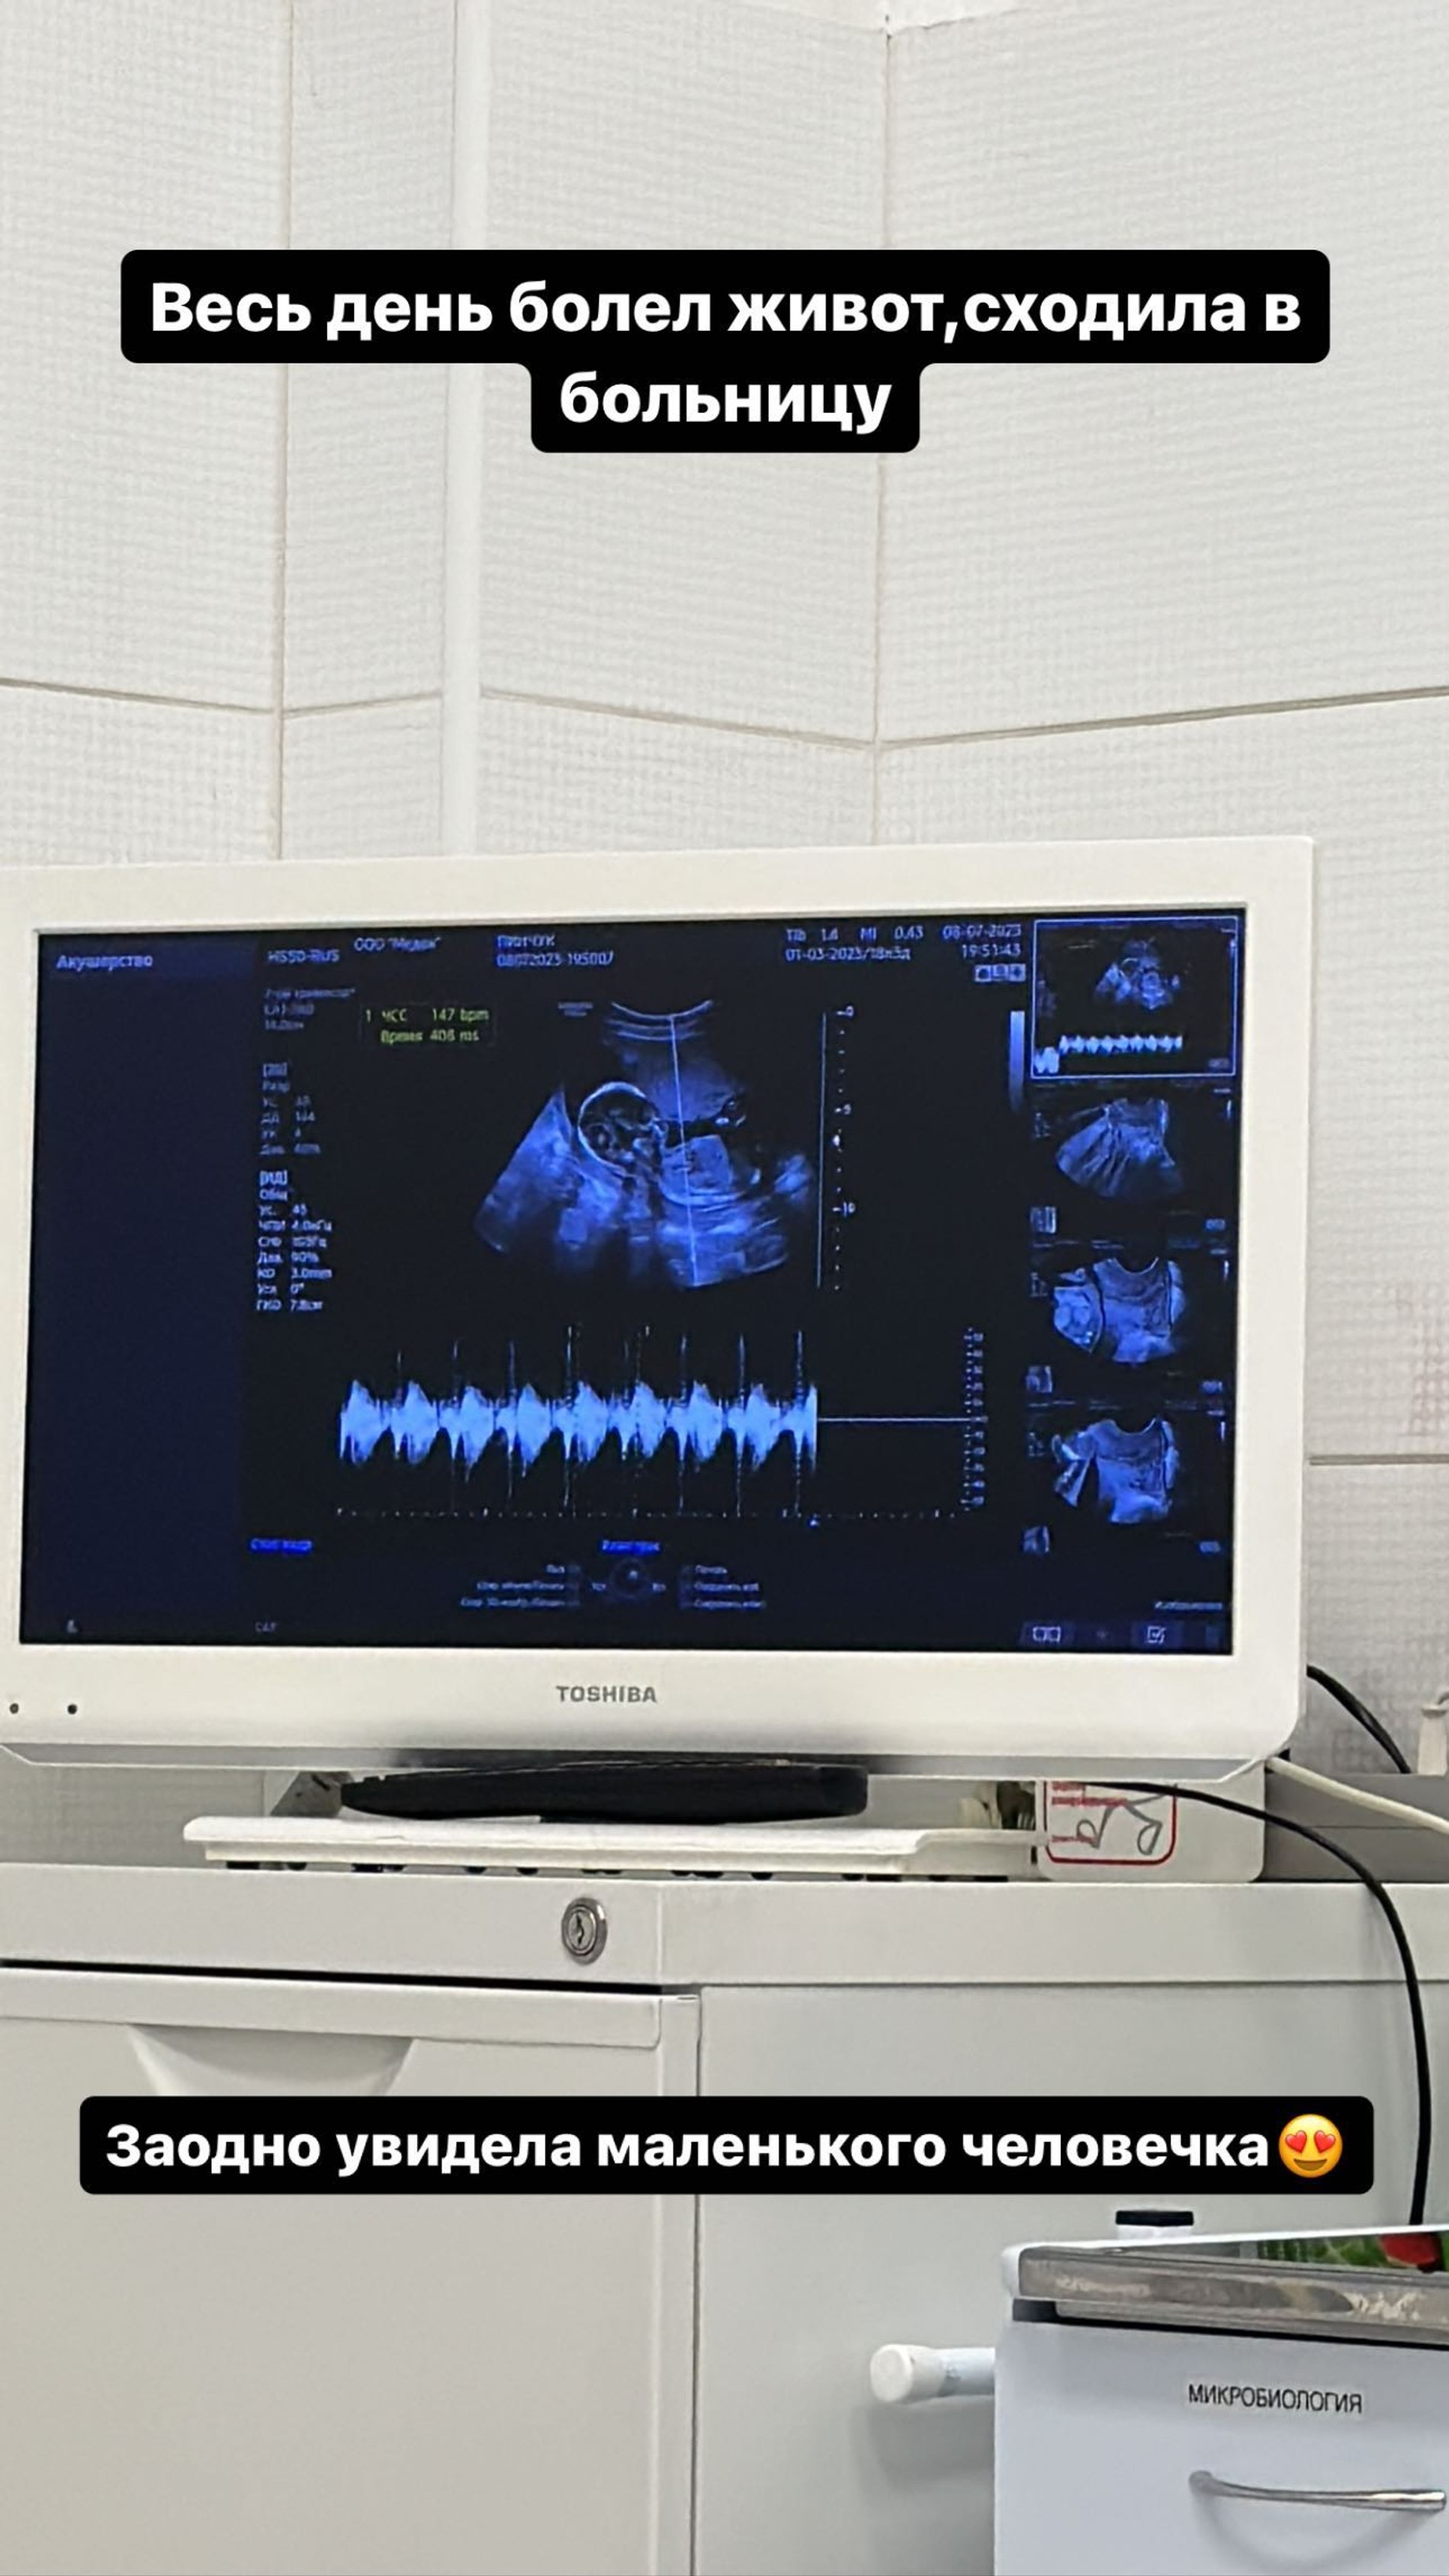

Попало в сторис и фото из кабинета УЗИ. Напомним, до этого Ирина уже выкладывала видео из той же локации, но быстро его удалила: по словам будущей мамы, подписчики тут же начали забрасывать ее своими сверхточными прогнозами пола ребенка. Надеемся, в этот раз атаки доморощенных специалистов удастся избежать.